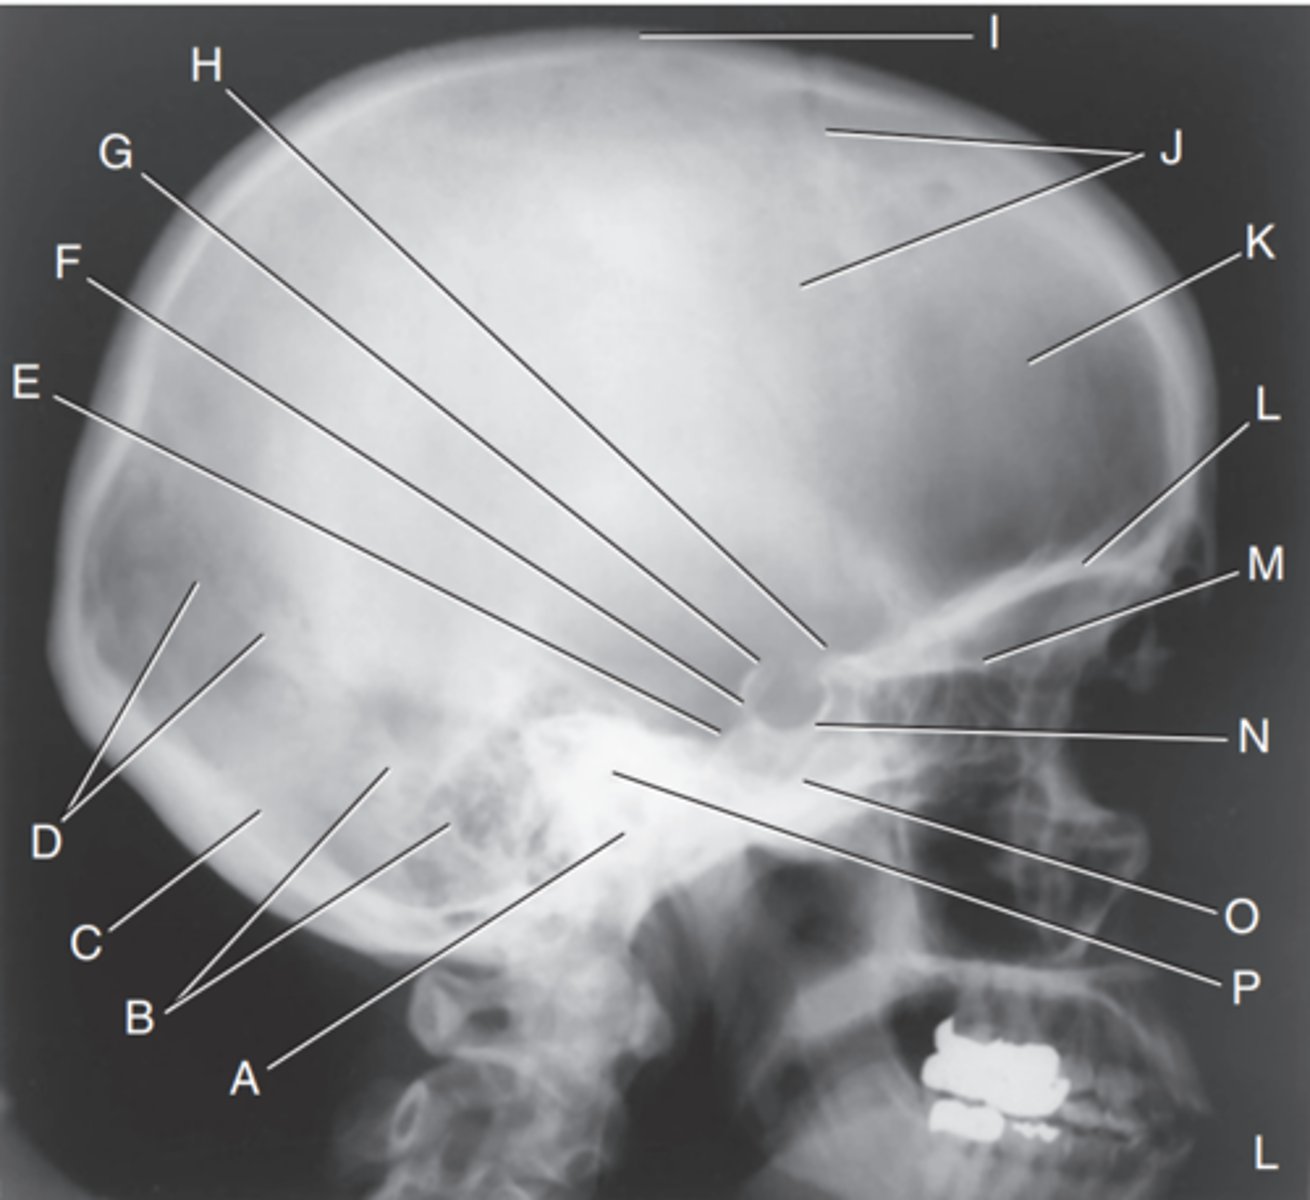

EAM

Label A

Mastoid portion of temporal bone

Label B

Occipital bone

Label C

Lambdoidal suture

Label D

Clivus

Label E

Dorsum sellae

Label F

Posterior clinoid processes

Label G

Anterior clinoid processes

Label H

Vertex of cranium

Label I

Coronal suture

Label J

Frontal bone

Label K

Orbital plates

label L

Cribriform plate

Label M

Sella turcica

Label N

Body of sphenoid (sphenoid sinus)

Label O

Petrous portion of temporal bone

Label P